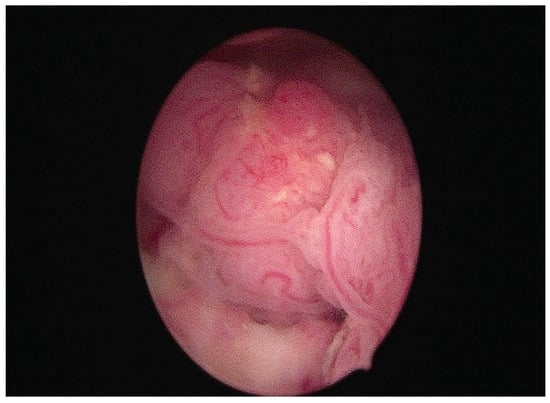

Among the new treatment options, some authors suggest performing an operative hysteroscopy with a pre-treated endometrium resection to promote complete cytoreduction before progestin therapy [16,35,38]. Figure 3 shows a hysteroscopic image of a neoplastic endometrial lesion occupying the uterine cavity, treated with a tissue removal device.

Figure 3.

Hysteroscopic view of endometrial cancer with exophytic growth within the uterine cavity, treated with a tissue removal device.